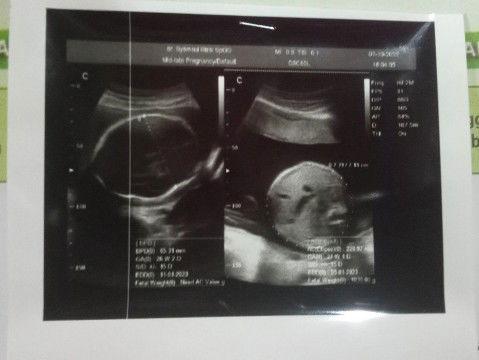

Hasil usg di usia kehamilan 27 week 2day

Ini hasil usg saya di usia 27 week 2day bunda2 alhamdulillah dedek a sehat dan smua a normal🥰dngn Jk baby girl 😘🥰ini kehamilan pertama saya☺️dokter a jga bilang dedek bayi a super aktif ,air ketuban a bagus, letak plasenta a jgk bagus . Di usia kehamilan 27week 2day BBJ a udah 1030.00 gr 🥰